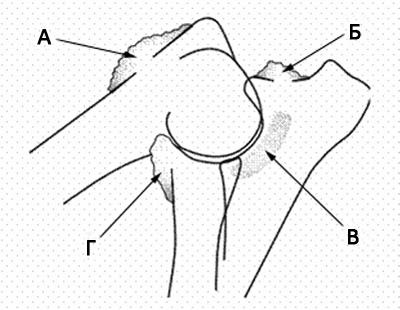

A - felkarcsont

B - sugár

B - ulna

A - koronoid

B - uncinatus

A - koronoid

B - hamulus

1 - sugara

2 - felkarcsont

3 - ulna